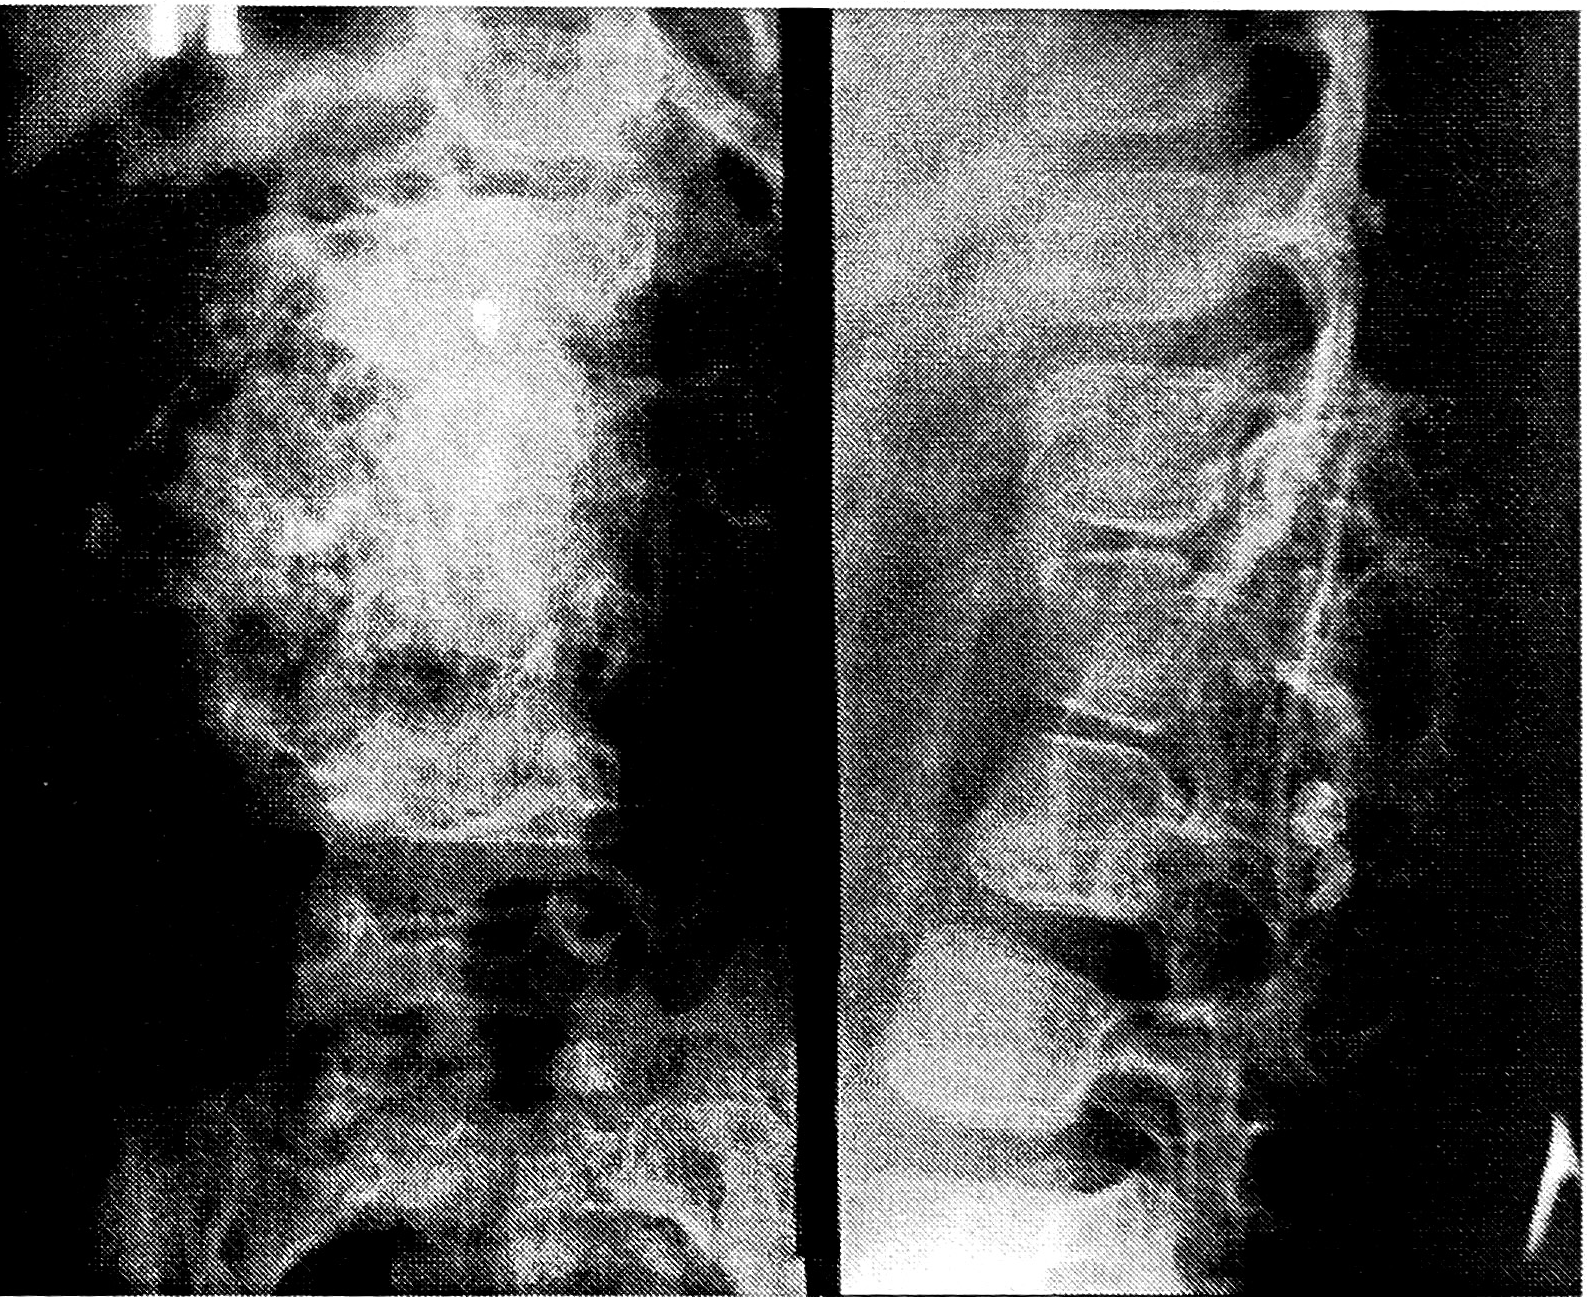

Рис. 3. Больная 7 лет с аневризмальной кистой кости дуги L2 позвонка.

Рентгенограммы: деструкция дуги позвонка с экстравертебральным компонентом, отделенным от мягких тканей скорлупой.